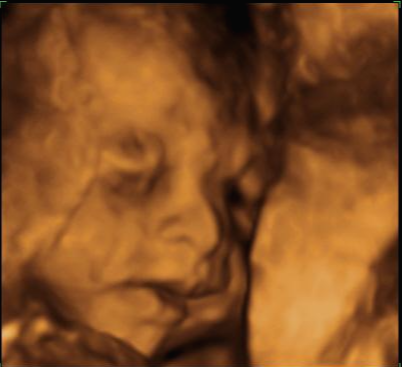

그리고 초음파 봐주시는 분께서 13주차가 되면 정확히 알 수 있으니 다음 주에 오라고 하셔서 일주일 뒤 다시 방문을 했습니다. (위에 사진은 12주 차 때 아들이라고 보여주신 초음파 사진이에요~ 화살표 보면 툭 튀어나와있는 부분을 보여주면서 아들이라고 하셨어요~)

일주만에 더 커있는 우리 트롱이~ 어찌나 꼬물꼬물 귀엽게 움직이던지 ㅎㅎ 트롱이 건강상태를 확인 후 다시 성별을 확인했는데 100프로 아들이라며 지금 병원에서 일을 하시고 경력이 25년 됐다고 믿음을 확실히 주셔서 초음파 검사가 끝나고 바로 부모님께 연락을 드리고 아들 옷 사러 갔어요 ㅋㅋㅋ

아 진짜 전문가는 다르구나~ 이렇게 이른 주수에도 성별을 알 수가 있구나 생각을 했지만 이 시기 때는 성별을 정확히 알 수 없다는 글들을 봐서 살짝~ 의심스럽기도 했지만 그래도 100프로라니깐 ㅎㅎ 믿어보았어요~ 근데 위에 사진을 보면 성별을 알 수 있는 각도 법이 있는데 각도가 딸 같아서 긴가민가~하긴 했지만 의심은 잠시! 전문가 분을 믿기로 ㅋㅋㅋㅋ